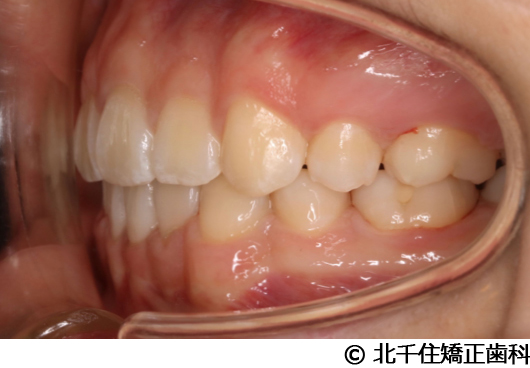

【症例2】上顎前突症

- 治療前

- 治療中

- 治療後

- 治療名

- 上顎前突症

- 費用

- 1,399,000円(税込)

- 期間

- 3年6ヵ月

- 治療回数

- 42回

- 通院頻度

- 1ヵ月ごと

- 年齢・性別

- 19歳10ヵ月・男性(初診時)

治療内容

-

患者様の症状

主訴:出っ歯、口元の突出、横顔をきれいにしたい

治療方法

骨格性の上顎前突、上下顎第一小臼歯4本及び上顎第二大臼歯を抜歯して矯正用アンカースクリューを併用してワイヤー矯正治療(セラミックブラケット)。

治療結果

骨格性上顎前突に対し、抜歯および矯正用アンカースクリューを併用した矯正治療により歯列および咬合関係の調整を行った症例である。治療後は保定装置を使用し、歯列および咬合の安定維持を目的として定期的な経過観察を行っている。

※治療結果は個人差があります。

治療を行う上での注意点(リスク・副作用)

歯磨き不良に伴うカリエスや歯周病、顎関節症、歯根吸収など。